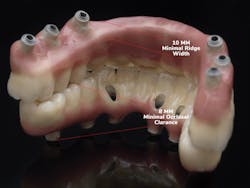

Start with bite blocks, making sure that each arch bite block is the thickness required of the desired prosthesis plus 1.5 mm thickness per arch. If you are not planning on opening vertical, you can also use an existing denture or a duplicate of that denture, but always do a reline impression. You must be prepared to consider opening vertically, as it may be necessary for many prosthetics. Use Table 1 to identify bite blocks that are the approximate dimensions for the prosthetic goal. For example, if you are proposing a monolithic zirconia hybrid, the bite block needs to have an occlusal thickness of at least 8 mm, a buccal-lingual width of 10 mm, and a minimum wall thickness from the proposed screw hole of 3 mm buccal and lingual.

Table 1: Implant-supported prosthetics—dimensional requirements for wall thickness

Occlusal clearance: tissue to opposing | Buccal-lingual width | Buccal and lingual width from center screw hole | |

Porcelain-fused-to-metal hybrid | 7 mm | 8 mm | 2.5 mm |

Zirconia hybrids | 8 mm | 10 mm | 3 mm |

Smart composite hybrid | 10 mm | 9 mm | 3 mm |

Conventional hybrid | 11 mm | 9 mm | 3 mm |

Denture over Hader bar | 11 mm | 11 mm | 4 mm |

Denture over locator bar | 12 mm | 11 mm | 4 mm |

Denture with locators direct to implants | 10 mm | 10 mm | 3 mm |